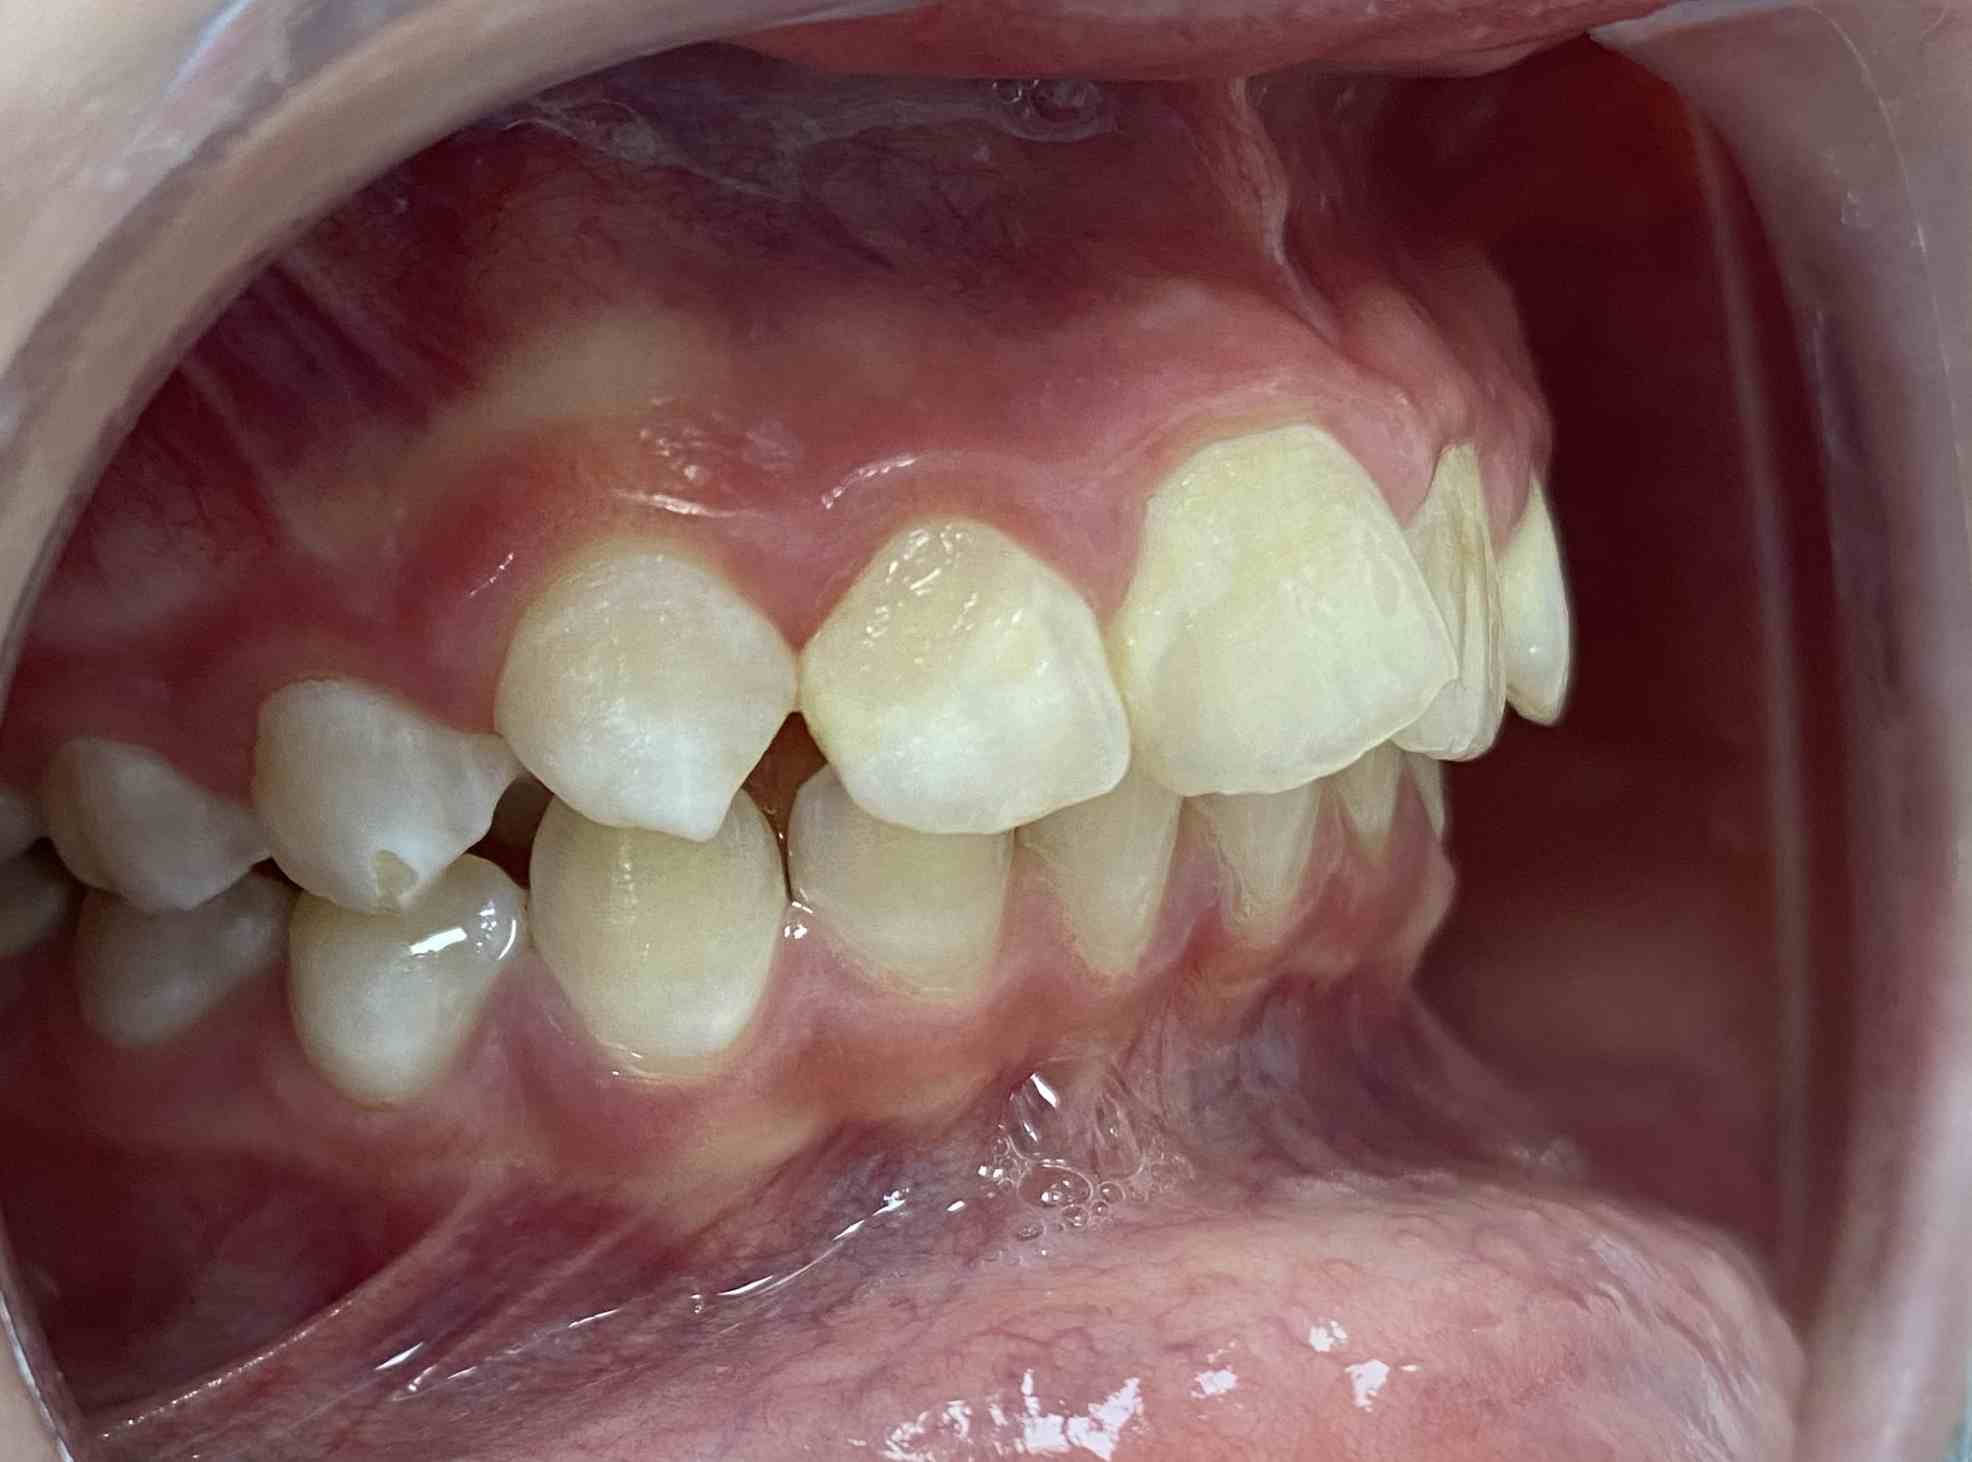

Pic.16. Mesial position of tooth 11 with lack of space in the dental arch.